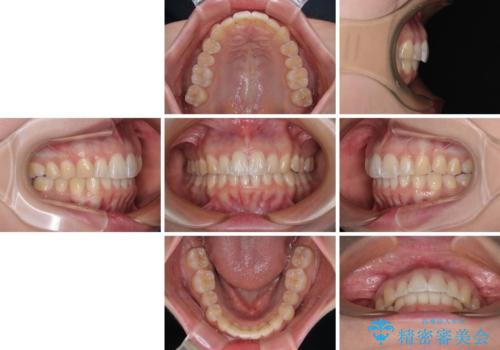

前に飛び出して目立っている前歯を整える インビザライン矯正治療

前歯の形が台形であり、歯列が整ったところでブラックトライアングルが目立つ仕上がりとなったため、IPR(歯と歯の間を削る処置)によって歯の形態を修正し、隙間の目立たない歯列に仕上げることができました。